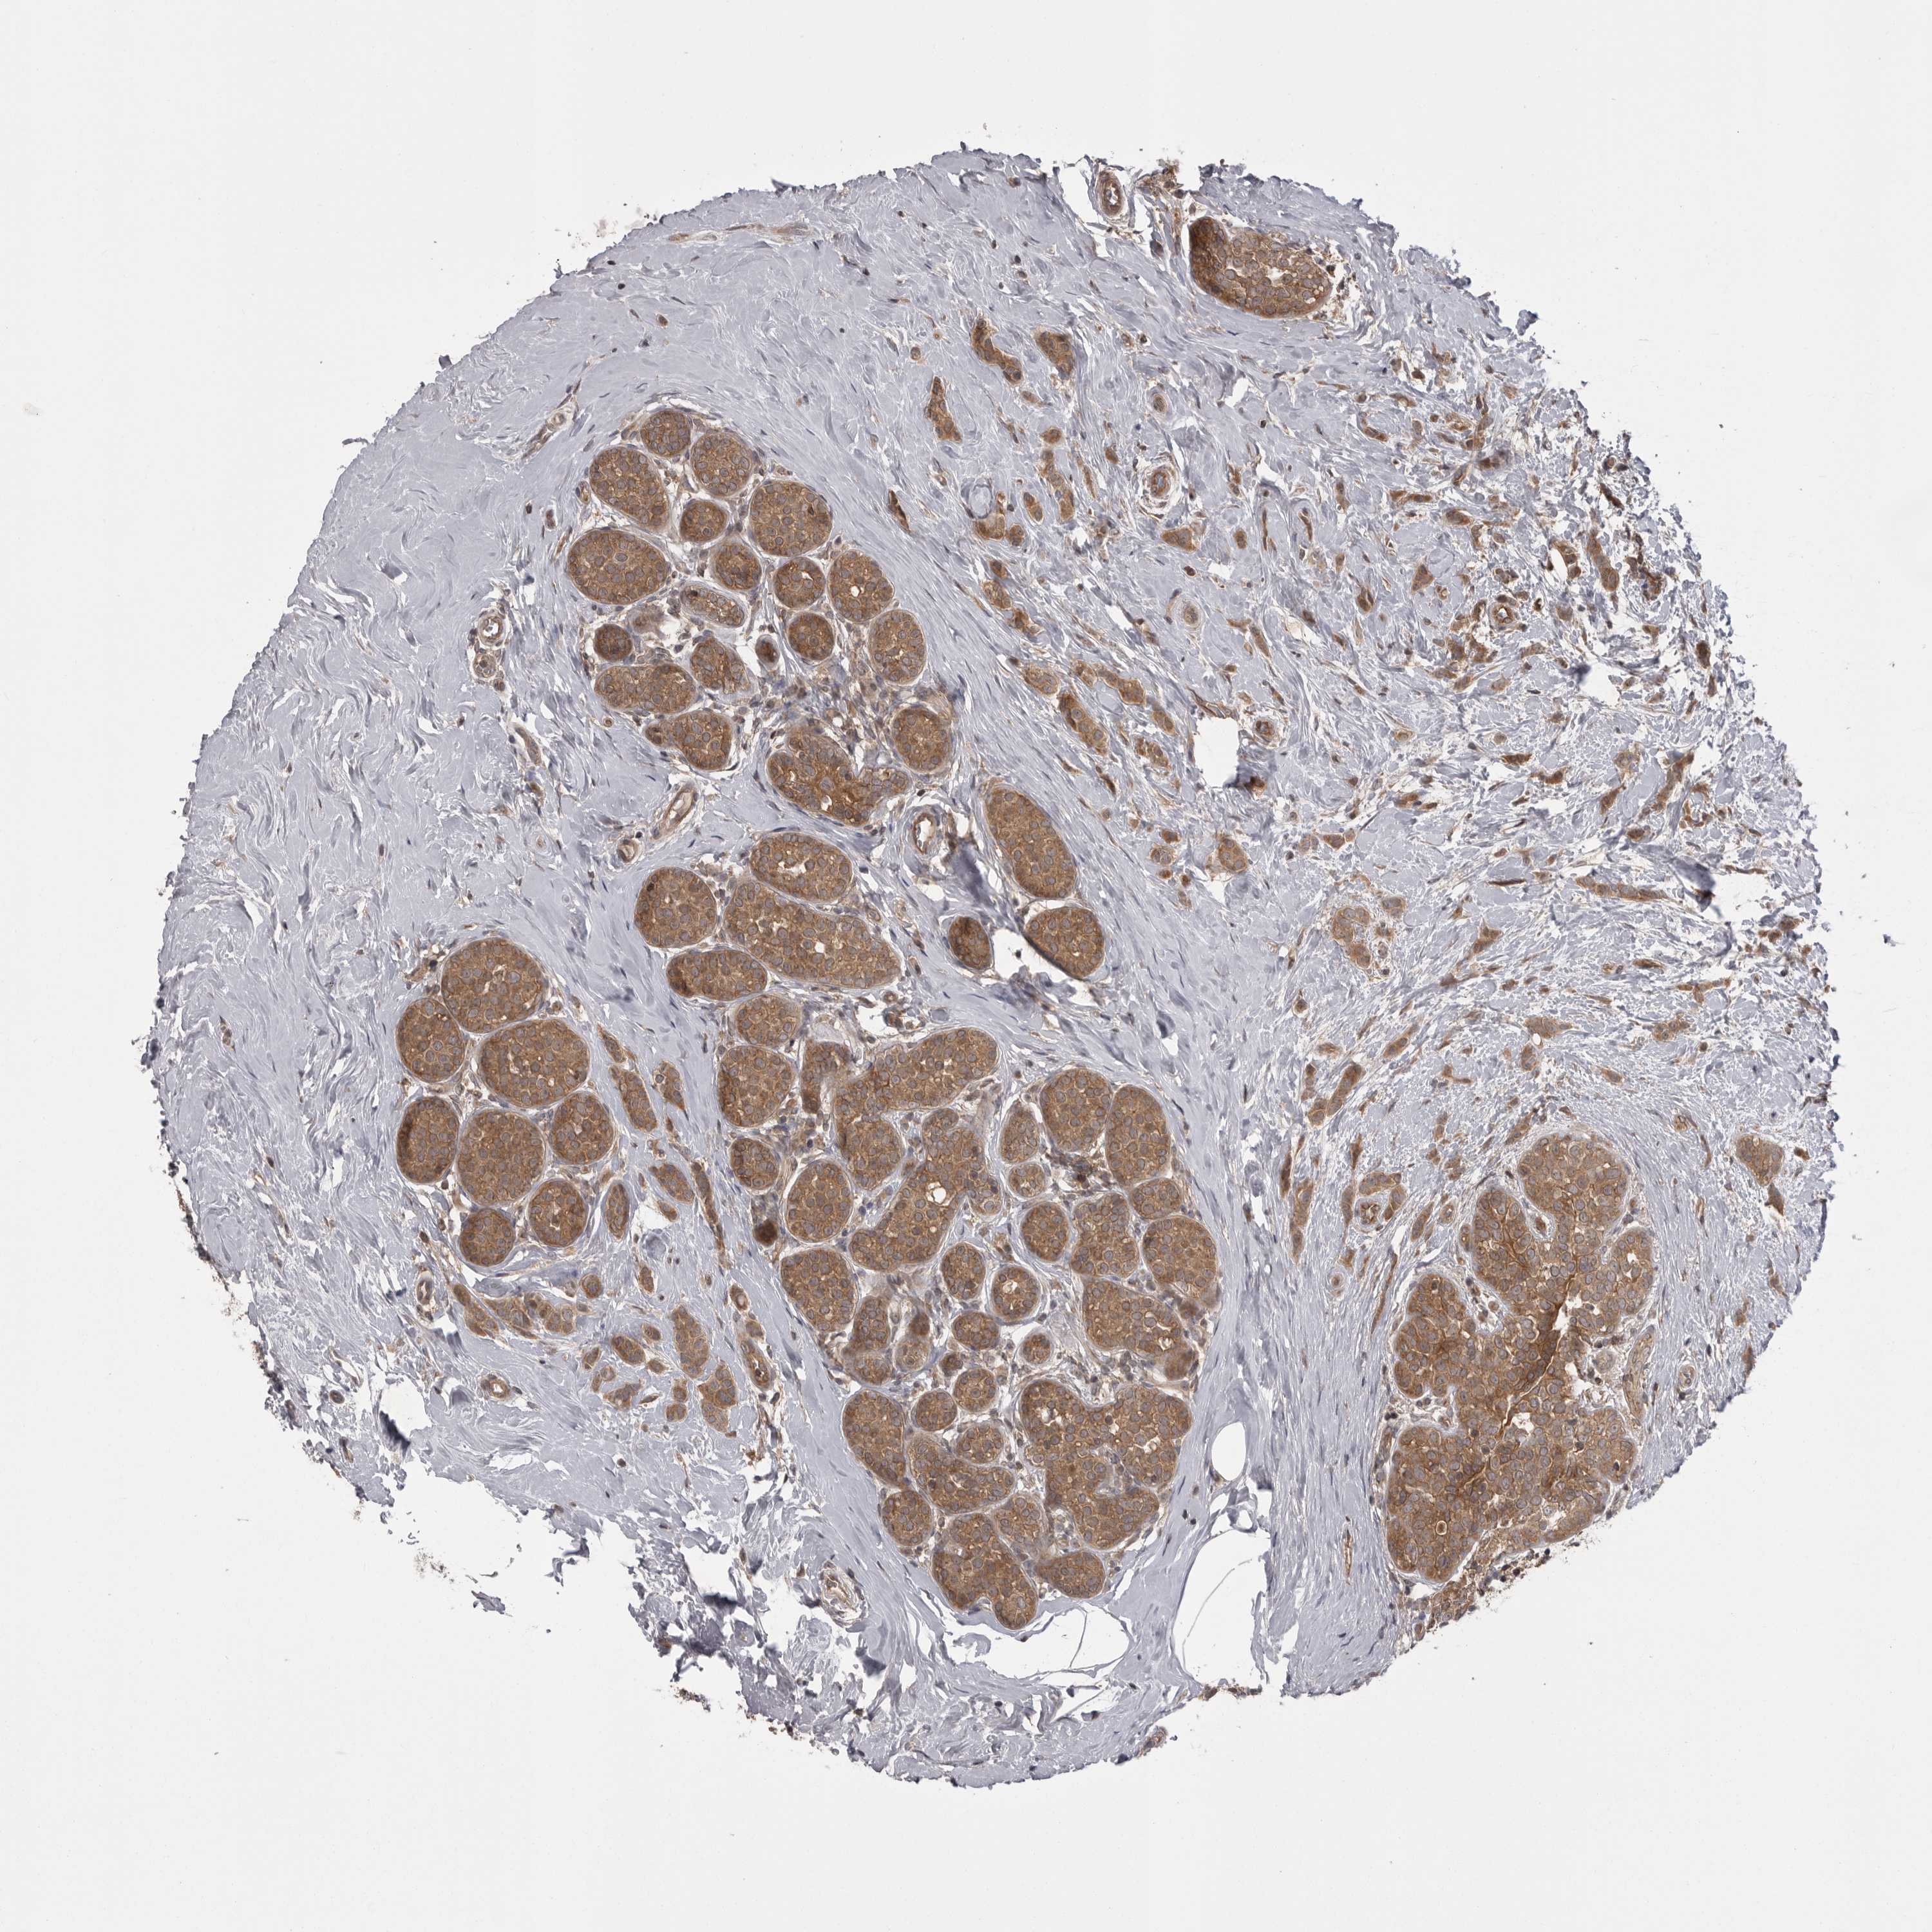

CANCER BREAST CANCER Show tissue menu

BRCA TCGA BRCA VALIDATION PROTEIN EXPRESSION